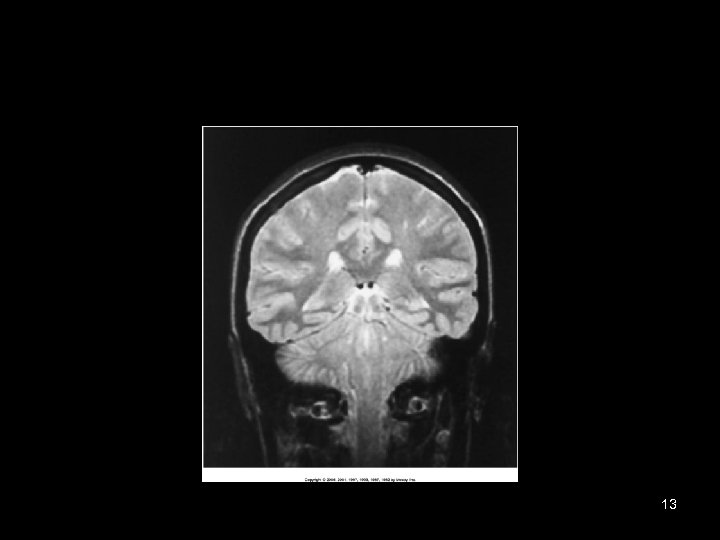

13